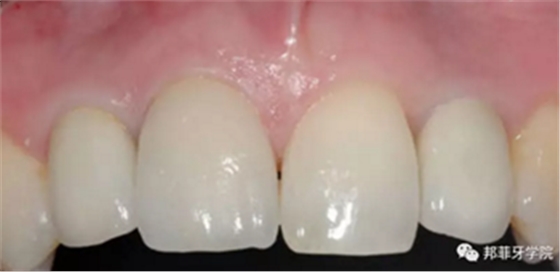

6年后效果穩(wěn)定,患者滿意(圖16)。

圖 16-1: 六年后復(fù)查

圖 16-2: 六年后復(fù)查